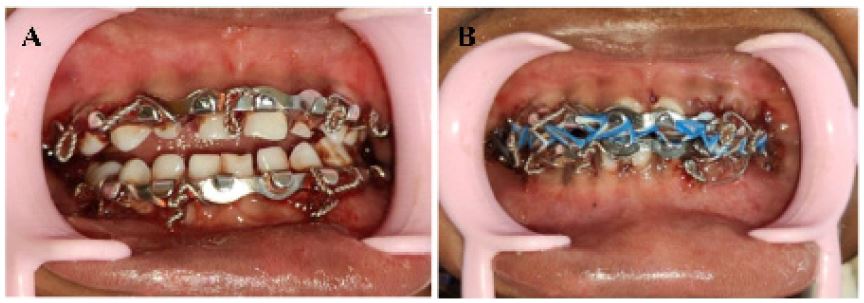

After a thorough clinical and radiographic examination, it was planned to manage the condition using the non-surgical closed reduction technique of Inter-Maxillary Fixation (IMF). Fractured fragments were reduced under local anesthesia (2% Lidocaine with 1:200000 adrenaline) and chairside sedation with Midazolam (0.5 mg/kg) (Mezolam - Neon Laboratories Ltd.). Prestretched 26-gauge stainless steel wire at the optimum lengths for the maxilla and mandible was used to secure the pediatric arch bars. Elastics (Blue, 1/4”-3.5 Oz) were placed to secure occlusion, as they are assumed to be better tolerated in children with equivalent outcomes of fracture healing and mandibular function (Figure 4A, 4B). The patient was kept on a soft diet, oral hygiene instructions were given and analgesics were prescribed.

Figure 4: (A-B) Intra-oral photograph after the Arch bar fixation.